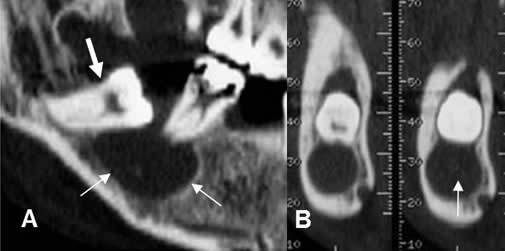

Fig 63. Ameloblastoma.

A: Panorámica de dentascan y B: TAC reconstrucción transversal. Lesión lítica, unilocular, bordes mal definidos (Flechas gruesa) y que crece por expansión, a nivel de la línea media y que ocasiona ruptura de la cortical. (Flechas delgadas).

Fig 64. Ameloblastoma.

Ortopantografía. Lesión quística y multilocular, de septos delgados, en el cuerpo de la mandíbula. En la parte superior se aprecia, erosión de la cortical del hueso. (Flecha delgada).